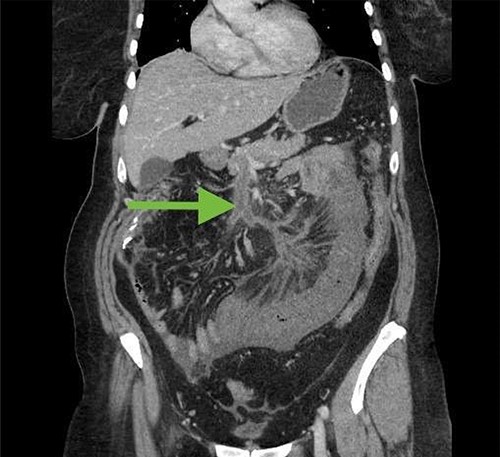

Two weeks after discharge, the patient returned with crampy abdominal pain. She was moderately tender on examination. White blood cell count was 15 000 and lactic acid was elevated at 3.5 mmol/l. CT scan of the abdomen and pelvis revealed an intraluminal filling defect of the superior mesenteric vein and portal vein not present on prior CT, consistent with acute venous thrombus (Fig. 3). There was also a long segment of concentric wall thickening of small bowel with mesenteric edema. The patient was taken to the operating room and had a segment of ischemic small bowel resected. She was also started on anticoagulation. Her abdomen was left open and she was taken back to the operating room a couple days later, at which time an anastomosis was created and her abdomen was closed.

CT abdomen/pelvis 2 weeks after initial surgery demonstrating superior mesenteric vein thrombosis (arrow) and a loop of thickened small bowel consistent with ischemia.